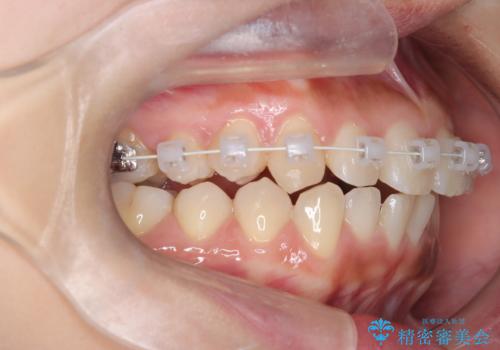

臼歯部の反対咬合を改善|MARPEによる上顎急速拡大+審美ワイヤー矯正

- 患者様は、奥歯(臼歯部)の反対咬合を主訴に来院されました。反対咬合は、噛み合わせのズレや顎の成長に影響を与える可能性があるため、早期の治療が重要です。診断の結果、上顎の幅が不足していることが原因と判明し、MARPE(骨固定式上顎急速拡大装置)を用いて上顎を広げる治療を計画しました。その後、歯列の調整のために審美ワイヤー矯正を行う方針としました。

MARPEを使用して上顎を拡大し、適切な歯列のスペースを確保しました。この拡大によって、反対咬合が改善され、正常な噛み合わせへと誘導できました。その後、目立ちにくいブラケットと白いワイヤーを使用した審美ワイヤー矯正を行い、歯列を整えました。治療が進むにつれ、噛み合わせのバランスが良くなり、見た目も自然な仕上がりに。